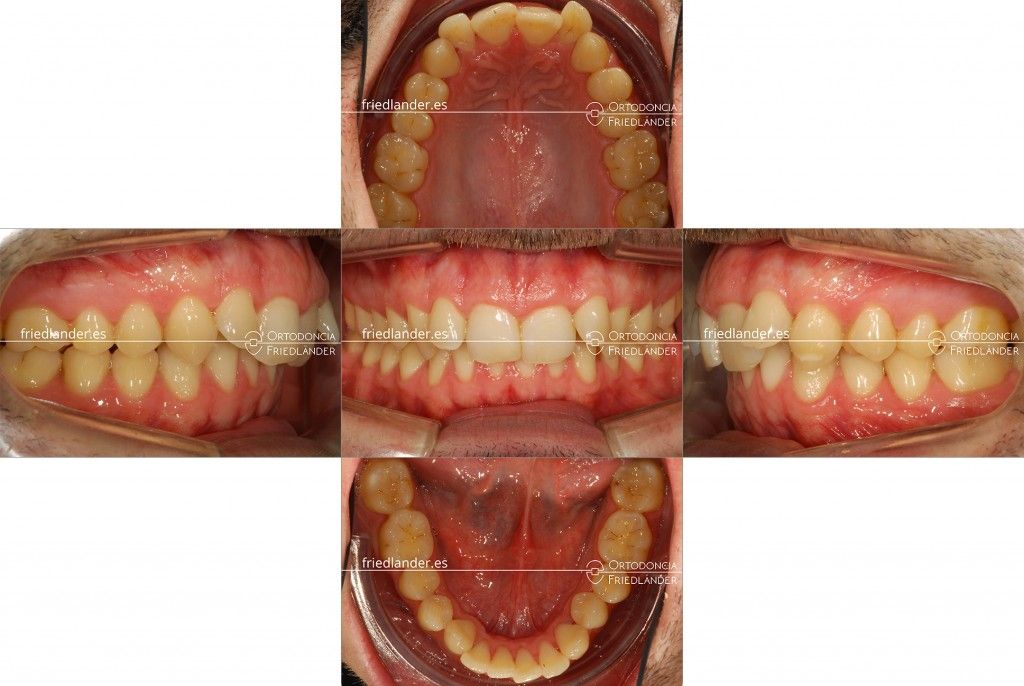

Al explorarlo clínicamente en la primera visita se observó que el problema más marcado es la clase II esquelética y dental (mandíbula retruída), una sobremordida aumentada y un apiñamiento dental ligero. El perfil del paciente era un perfil retrusivo con labios finos que no permitían más retrusión de los mismos. Un detalle importante es que los incisivos inferiores estaban protruidos o inclinados hacia adelante, este detalle es muy determinante en la decisión de qué tipos de movimientos podemos, o no, hacer con la ortodoncia.

Al cabo de 22 meses de tratamiento hemos conseguido una correcta clase I y el paciente estaba muy contento con los resultados.